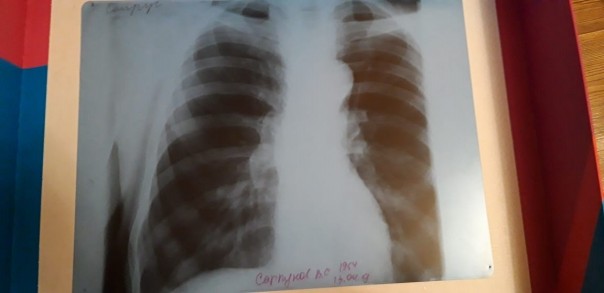

При этом, когда Василий Сапрунов был в больнице в Невьянске после того, как ему стало плохо на даче, там ему сделали снимок, на котором нет никакого протеза.

— Его спросили: а кто вам сказал, что у вас стоит эндопротез. Его изначально не было, сказали нам в больнице Невьянска, — говорит Сергей. — Получается, отец год промучился без этого эндопротеза, а мы при этом заплатили деньги за бесплатный протез.

На снимке, который сделали в больнице в Невьянске, протеза не видно